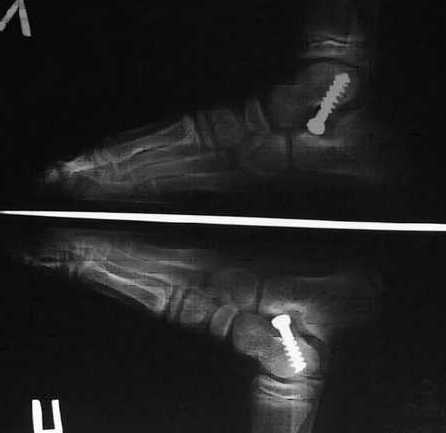

Да,Андрей,выглядит как шутка. Уж очень всё просто: банальный шуруп, 8мм рарез, операция 20 минут на 2х стопах, пациент ходит на 2-3 сутки. Фантастика? Но это на самом деле дёшево, эффективно, элегантно и просто. Один раз увидишь -будешь делать.